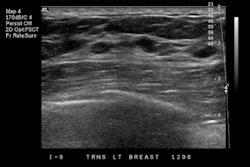

The U.S. Food and Drug Administration (FDA) has cleared Koios Medical's Koios DS, an artificial intelligence (AI)-based software platform used to diagnose thyroid and breast cancer.

The company said Koios DS was developed using ultrasound data from a network of 48 sites around the world, with the aim of aiding physicians in diagnosing diseases and improving speed to treatment while reducing avoidable surgeries.